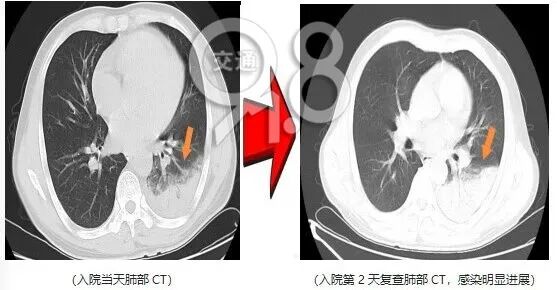

半年前,爱鸟人士刘先生开始养宠物鸟。出现咳嗽、高热等症状后,前往医院就诊发现,左下肺有明显肺泡渗出。

病情进展迅速,后出现咯血、呼吸衰竭等表现。通过肺泡灌洗并基因检测后,发现是鹦鹉热衣原体感染,针对性治疗后,目前已恢复出院。